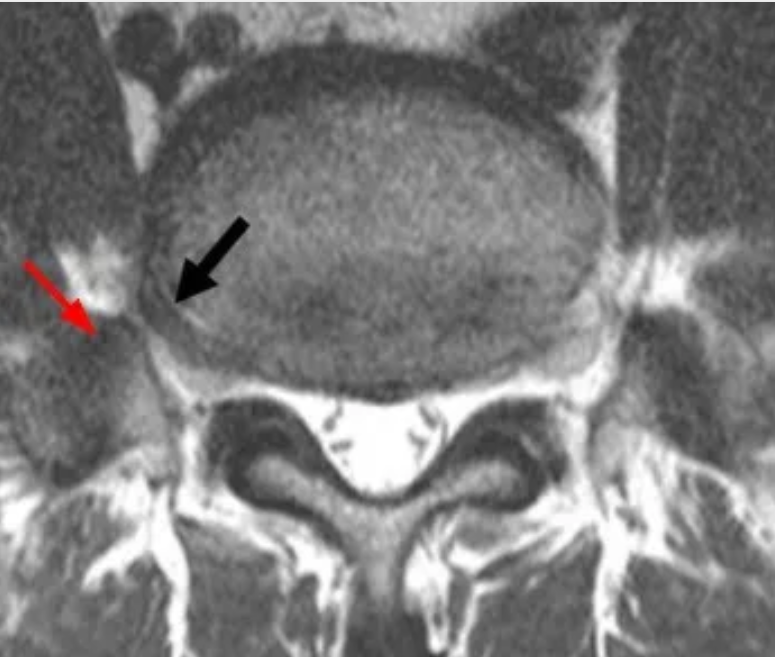

L5椎间盘呈远外侧型突出(黑箭)并与粗大的L5横突协同压迫L5神经根